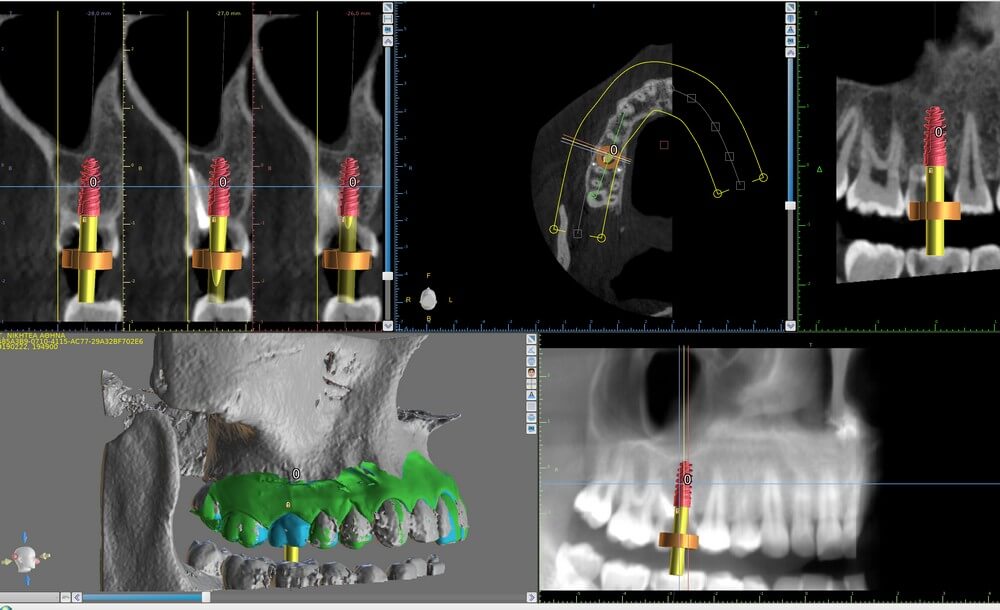

Ψηφιακά καθοδηγούμενη τοποθέτηση εμφυτευμάτων

Ένα ακόμα πεδίο στο οποίο έχει συμβεί επανάσταση με την ψηφιακή τεχνολογία είναι αυτό της εμφυτευματολογίας, όπου με την αξιοποίηση ειδικών προγραμμάτων (softwares), βελτιώνεται πολύ η προβλεψιμότητα, η ασφάλεια και η ποιότητα.

Τα ειδικά προγράμματα λογισμικού για κατευθυνόμενη τοποθέτηση εμφυτευμάτων συνδυάζουν τα δεδομένα από την τομογραφία κωνικής δέσμης και τις ενδο- ή έξωστοματικές σαρώσεις και γίνεται πλήρης σχεδιασμός για την ακριβή, επιθυμητή, θέση τοποθέτησης των εμφυτευμάτων, μέσω της κατασκευής και χρήσης ειδικών χειρουργικών ναρθηκών που τοποθετούνται κατά τη χειρουργική διαδικασία στο στόμα του ασθενούς. Τα ποικίλα εργαλεία του λογισμικού διευκολύνουν την παραγγελία του κατάλληλου μεγέθους και γεωμετρίας των εμφυτευμάτων και δίνουν σημαντικές πληροφορίες σχετικά με το χώρο και την επιλογή του υλικού των επιεμφυτευματικών αποκαταστάσεων με εξαιρετικά υψηλή αξιοπιστία. Επίσης αποφεύγεται ο πιθανός τραυματισμός ευαίσθητων ανατομικών δομών και μειώνεται σημαντικά ο χειρουργικός χρόνος, κάτι που ικανοποιεί και τον ασθενή. ‘Οπως λέει και η φράση: «Αποτυχία κατά τον σχεδιασμό είναι σαν να σχεδιάζουμε να αποτύχουμε» και η τεχνολογία προσφέρει στον οδοντίατρο τη μοναδική δυνατότητα να "πραγματοποιεί" τα χειρουργεία, προτού καν έρθει σε επαφή με τον ασθενή.